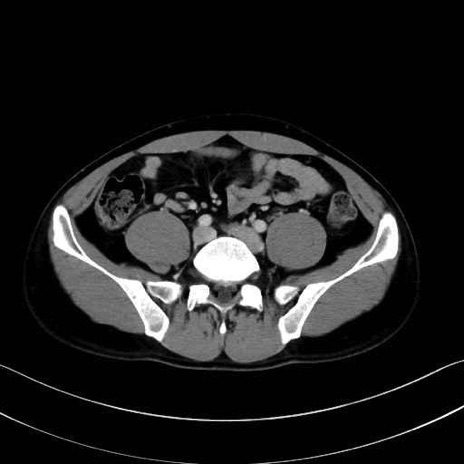

2. 腸腰筋群と骨盤底筋

大腰筋 (Psoas major)

腸骨筋 (Iliacus)